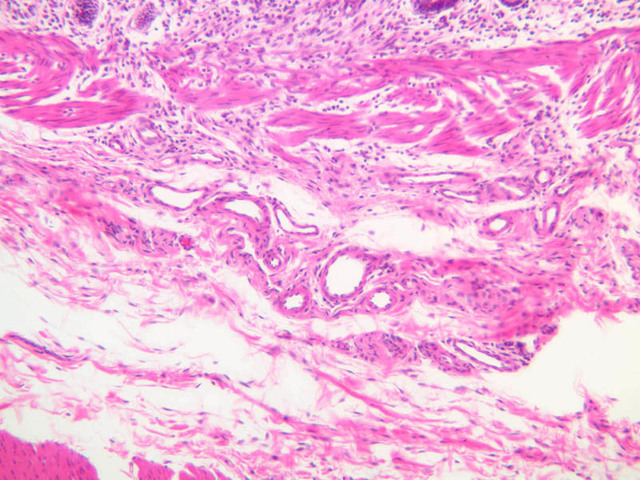

Blood passes from the elastic arteries via arteries of intermediate type into the muscular (distribution) arteries. Locate and examine a muscular artery in slide A-28 (Renal artery & vein, H&E [2.5x, 10x-labeled, 20x, 40x-labeled] [10x-labeled, 20x, 40x]; AF [10x-labeled, 20x, 40x]). Note that the tunica intima is separated from the tunica media by a thick internal elastic membrane which has a scalloped appearance. The tunica media consists of many layers of smooth muscle cells arranged concentrically in a spiral fashion (A-28, H&E [2.5x, 10x-labeled, 20x, 40x] [2.5x, 10x, 20x, 40x, 40x] [2.5x, 10x, 20x]). An external elastic membrane is present, but is thinner and less complete than the internal elastic membrane. The tunica adventitia is about equal in size to the media in this vessel and is more intensely eosinophilic in its staining properties. Note the appearance of small blood vessels in the outer part of the tunica adventitia. You may also be able to see occasional nerve fibers.

Veins are generally divided into small, medium, and large categories, though this division is not as readily based upon structural differences as among arteries. Examine a section of medium-sized vein (B-83, spermatic cord [2.5x, 10x, 20x-labeled, 40x] [10x, 20x, 40x] [2.5x, 10x, 20x, 40x]). The tunica adventitia, composed mainly of collagenous fibers cut obliquely or transversely, may be the thickest of the three coats. A thin internal elastic membrane can be seen in places around the vessel, but it is much less prominent than the membrane of the companion artery. No external elastic membrane is distinguishable in the vein. Compare the features of artery and vein: thickness of wall, size of lumen, amount of musculature, etc. The vein has a relatively wide lumen and a thin wall because it carries large volumes of blood at low pressures.

Large veins have a very narrow tunica intima and only a few layers of muscle and fibers in the tunica media (A-28, H&E [2.5x, 10x-labeled, 20x, 40x], AF [2.5x, 10x, 20x, 40x]). Its chief coat, as in smaller veins, is the tunica adventitia, but in this case, the coat is composed mostly of longitudinal muscle fibers. Some other large veins, particularly those of the cranial cavity, lack muscle and thus differ from the venae cavae. The structure of veins generally and large veins in particular is more variable than arterial structure.